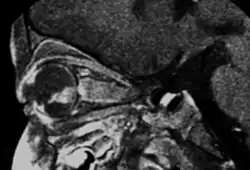

MRI pattern of retinoblastoma with optic nerve involvement (sagittal enhanced T1-weighted sequence)

If the eye examination is abnormal, further testing may include imaging studies, such as computerized tomography (CT), magnetic resonance imaging (MRI), and ultrasound.[30] CT and MRI can help define the structure abnormalities and reveal any calcium depositions. Ultrasound can help define the height and thickness of the tumor. Bone marrow examination or lumbar puncture may also be done to determine any metastases to bones or the brain.

Traditional ultrasound B scan can detect calcifications in the tumour while high-frequency ultrasound B scan is able to provide higher resolution than the traditional ultrasound and determine the proximity of the tumour with front portion of the eye. MRI scan can detect high-risk features such as optic nerve invasion; choroidal invasion, scleral invasion, and intracranial invasion. CT scan is generally avoided because radiation can stimulate the formation of more eye tumours in those with RB1 genetic mutation.[37]